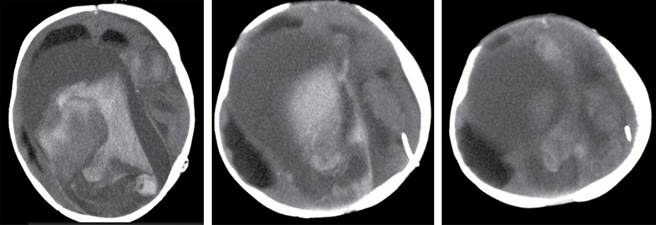

Cinco meses después de internamiento anterior, el paciente es llevado al servicio de Urgencias con signos de hipertensión endocraneana, por lo cual se ingresó a la UCI. En imagen de tomografía cerebral se identificó hemorragia intracraneana masiva (Figura 4), lamentablemente el paciente se deterioró progresivamente llegando a muerte cerebral y fallecer.